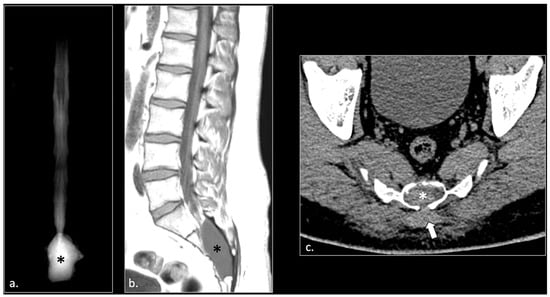

MRI in Chronic Pudendal Neuralgia: Diagnostic Criteria and Associated Pathologies

by Michele Gaeta, Sofia Turturici, Karol Galletta, Carmelo Geremia, Attilio Tuscano, Aurelio Gaeta, Marco Cavallaro, Salvatore Silipigni and Francesca Granata

Background/Objectives: Chronic pudendal neuralgia is a relatively rare condition in the general population, with an incidence of 1%. Although diagnosis of pudendal neuralgia is mainly clinical, Magnetic Resonance Imaging (MRI) is commonly performed to obtain further information. However, clear criteria and guidelines for MRI diagnosis and the clinical–radiological correlation are still not definite. Methods: We reviewed 81 patients with chronic pudendal neuralgia, studied by an MRI designed protocol for a pelvis and pelvic floor examination. A key element of the protocol was the use of a diffusion-weighted imaging (DWI) technique with echo planar imaging (EPI) sequence (b-values of 0, 100, and 600) for the neurographic evaluation of the nerve. Results: MRI examination revealed DWI abnormalities in 42/81 patients. Pudendal nerve abnormalities were unilateral in 33/42 patients and bilateral in 9/42. Moreover, in 23/42 patients, pathologies related to a high probability of neuropathy have been identified. Conclusions: This study highlights the role of pelvic MRI as a valuable imaging modality in the evaluation of patients with chronic pudendal neuralgia. In the study protocol we propose, an essential role is played by the DWI technique, which improves the visual definition of the pudendal nerve and related anatomical structures. By focusing on anatomical visualization and structured image interpretation, our work provides a practical imaging-oriented contribution to a field in which standardized MRI evaluation is still lacking. Full article